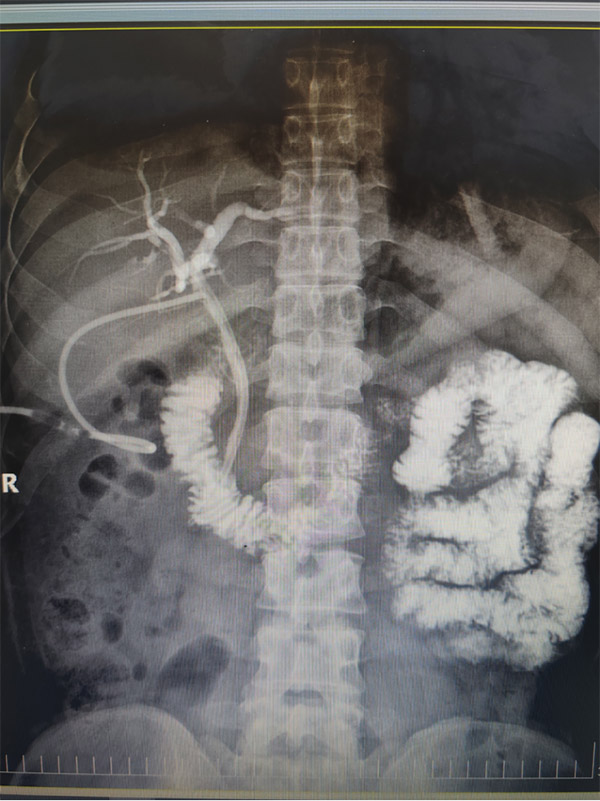

后T管造影证实了徐进院长关于Mirizzi综合征分型I型的判断。病人肝总管、胆总管完整通畅,无残余结石,治疗取得彻底成功。

▲术后T管造影证实保护胆管充分,没有结石残留